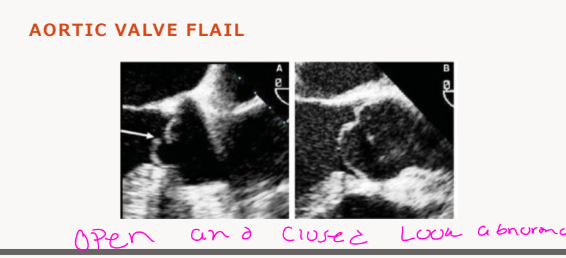

what is Aortic Valve Flail

Diastolic fluttering of the aortic cusp echoes,

abnormal systolic aortic leaflet movement, and

abnormal diastolic fluttering echoes in the left

ventricular outflow tract